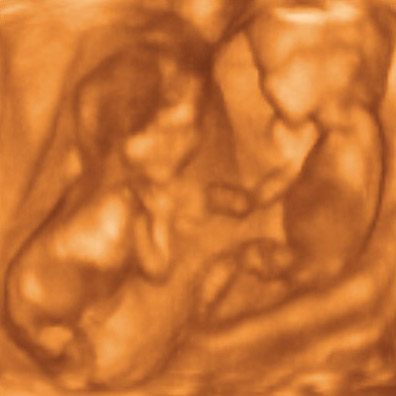

Benó, boldog hétfordulót... legalább 20 percet nézegettem a fényképet a babáidról, és annyira irigyellek... tök édesek, hogy egymással szemben vannak, és gondolom kommunikálnak is egymással. Azt felejtettem csak el, hogy egy vagy kétpetéjűek-e, de majd visszanézlek. Szóval el vagyok ragadtatva tőlük.

(lehet, hogy látni, hogy kétpetéjűek? Most arra tippelnék...